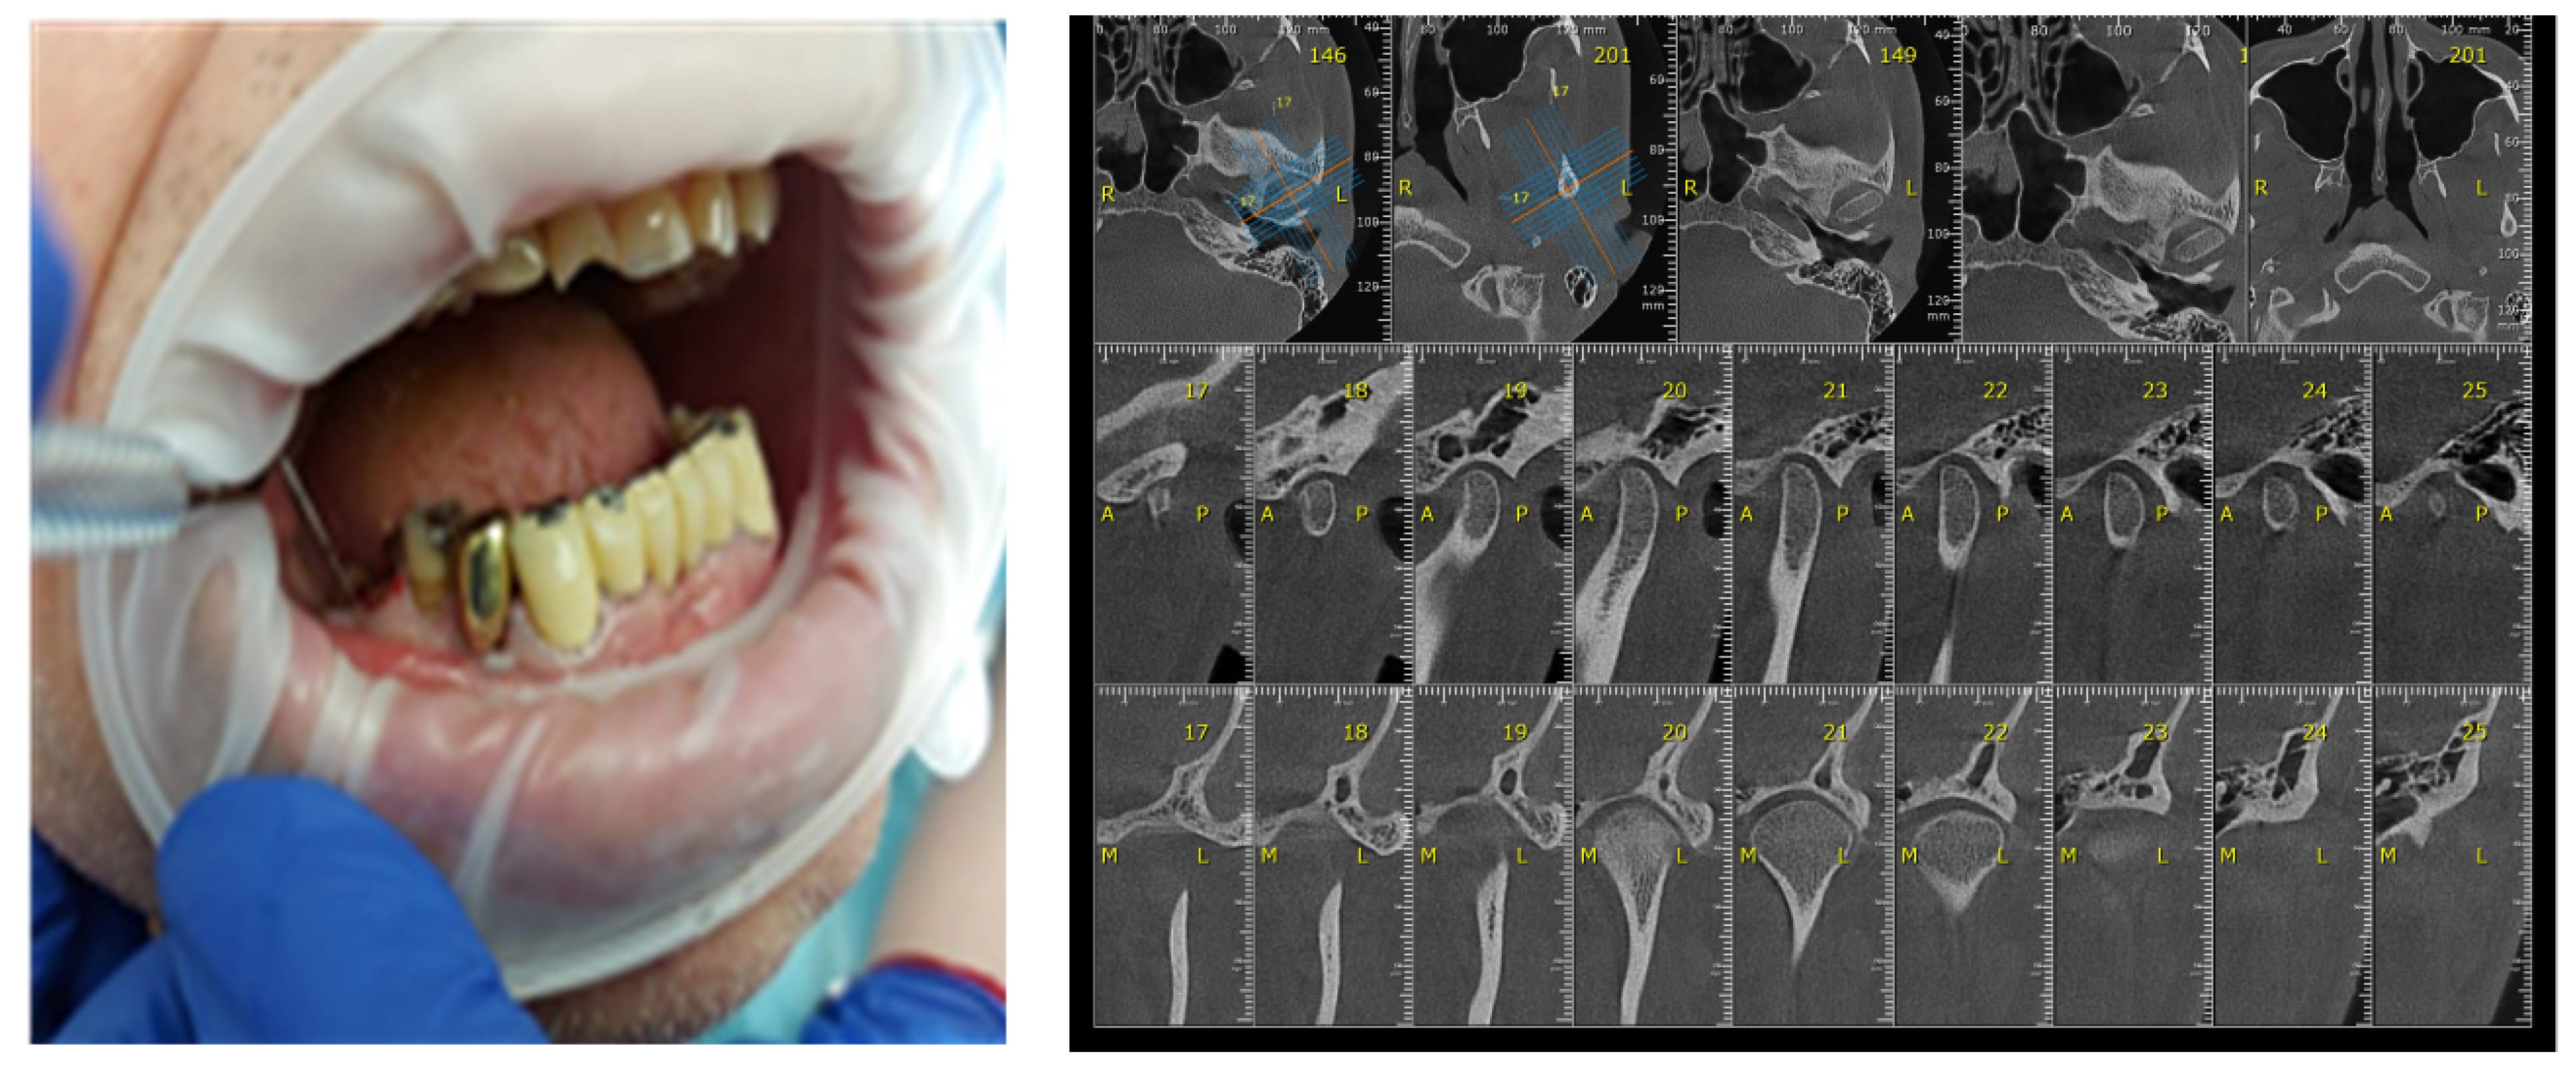

3. Materials and Methods

| CBCT | cone-beam computed tomography |